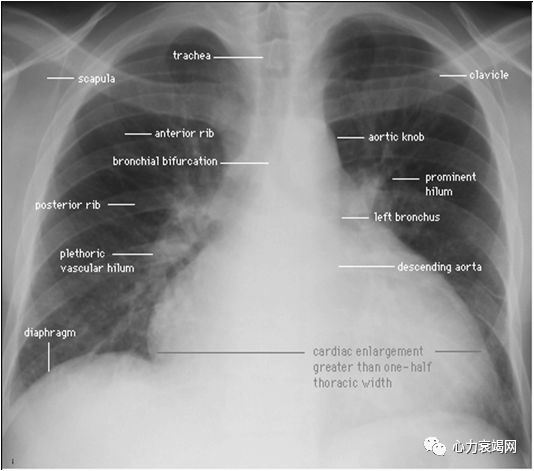

胸片

肺水肿、肺郁血、胸腔积液

心脏增大